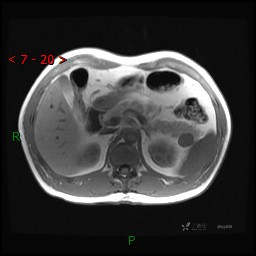

MRI(T1WI+T2WI-fs+DWI+ADC)